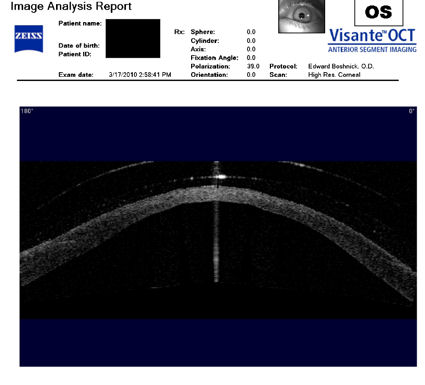

Следующие изображения были получены с использованием метода, называемого оптической когерентной томографией, или ОКТ. Прибор позволяет получить изображение в поперечном сечении путем сканирования передней части глаза (переднего сегмента) лучом света. Думайте об этом как об ультразвуке, использующем свет вместо звуковых волн для создания изображения живых тканей.

На изображении, приведенном непосредственно ниже, представлен снимок здоровой, неоперированной роговицы для сравнения со следующими изображениями эктатических роговиц после операции LASIK.

Изображения любезно предоставлены доктором Эдвардом Бошником, который посвятил свою практику восстановлению качественного зрения и информации о эктазия после операции LASIK .